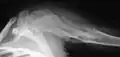

-

X-ray showing calcified enchondromas localized in finger a 37-year-old patient affected with Ollier disease -

X-ray showing enchondromas localized in the humerus of a 37-year-old patient affected with Ollier disease -

X-ray showing enchondromas localized in the lower part of the radius of a 37-year-old patient affected with Ollier disease -